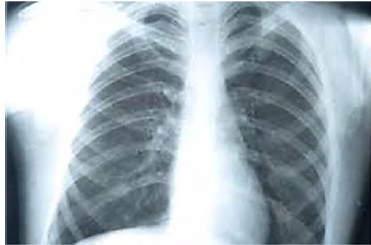

Um paciente etilista deu entrada no pronto-socorro com intensa dor na região torácica, associado a vômitos, após realizar grande esforço. A dor é localizada na região retroesternal e em abdome superior, de início agudo e de forte intensidade. Quanto a comorbidades, informa tratamento para úlcera gástrica há um ano. Queixa-se de odinofagia associada ao quadro de dor no peito. Ao exame físico, constatam-se abdome doloroso sem sinal de irritação peritoneal, PA = 150 mmHg x 100 mmHg, FC = 130 bpm, FR = 30 irpm e SatO2 = 93% AA. Realizou raios X de tórax, representado na imagem a seguir.

Disponível em: <https://tuasaude.com,br> . Acesso em: 12 nov. 2020.